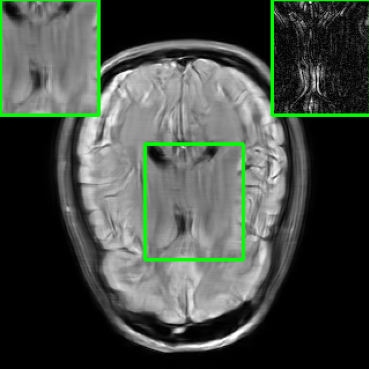

In addition to additive perturbations, the study presented in [32] underscores an additional potential source of instability that MoDL may face during testing. This source stems from changes in the measurement sampling rate, leading to perturbations in the sparsity of the sampling mask within [10]. Furthermore, in this paper, we consider another variation that MoDL could encounter during the testing phase, involving a shift in the k-space sampling locations within the matrix , resulting in the construction of a nonidentical forward operator for testing. For this case, , where . Figure 1 illustrates reconstructed images from the instabilities considered in this paper.

| PSNR = 29.8 dB | PSNR = 22.01 dB | PSNR = 20.28 dB | PSNR = 23.14 dB |

| (a) | (b) | (c) | (d) |

5.4 Visualizations

We now present visual samples from both the knee and brain datasets. Specifically, Figure 5 presents visual comparison of image reconstructions and their associated reconstruction errors within a closely examined region. Each image in the figure includes two inset panels in the top-left and top-right corners. The top-left inset panel, enclosed within a green bounding box, serves as a reference for the region of interest in the image. In contrast, the top-right inset panel depicts an error map in relation to the ground truth. Notably, our method stands out in its ability to capture the original image’s features, surpassing the performance of alternative methods (as also evident from the reported PSNR values). This visual comparison underscores the superior quality and accuracy of our approach in the robustification of the MRI image reconstruction task.